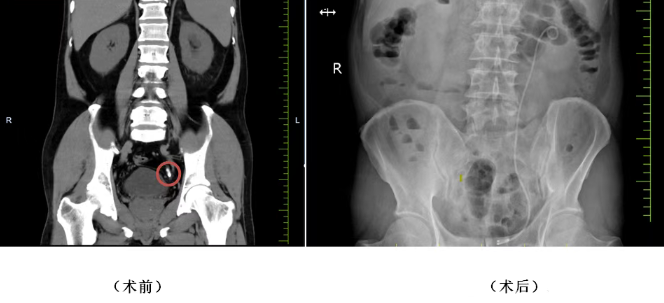

患者李女士(化名)因左側(cè)腰腹部間斷疼痛1年入院,檢查發(fā)現(xiàn)左側(cè)輸尿管腹段結(jié)石伴左腎積水,同時合并2型糖尿病,病情相對復(fù)雜。張寶主任團(tuán)隊先為其實施左腎造瘺術(shù),快速緩解尿路梗阻、控制感染,為后續(xù)手術(shù)創(chuàng)造安全條件。待患者身體條件穩(wěn)定后,團(tuán)隊通過經(jīng)尿道左側(cè)輸尿管鏡鈥激光碎石取石術(shù),在高清內(nèi)鏡下精準(zhǔn)定位結(jié)石,利用鈥激光高效擊碎并取出結(jié)石,同時置入輸尿管支架保障術(shù)后引流。術(shù)后患者排尿通暢,無發(fā)熱、腰痛等不適,順利康復(fù)出院。